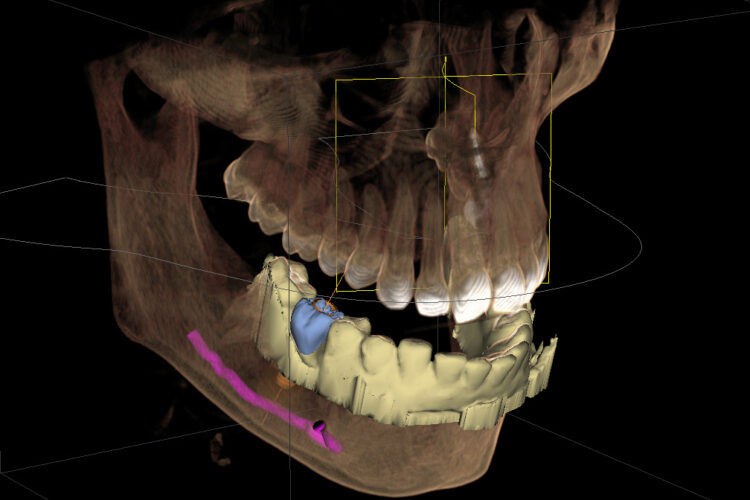

Еще осложнения могут быть, например, когда при установке импланта на нижней челюсти затрагивается (или сжимается) нижнечелюстной нерв. В такой ситуации у пациента появляются сильные болевые синдромы. Здесь, опять же, необходимо извлечь имплант. Но, самое страшное, что установка импланта с повреждением нерва влечет за собой онемение подбородка и щеки, которое может длиться долгое время, иногда годами.

Кроме нижнечелюстного нерва, при установке имплантата на нижней челюсти есть риск повредить артерию в подъязычной области. Кровотечение после повреждения артерии очень интенсивное, его сложно остановить, но самое страшное, что эту артерию сложно поймать. Потому что, когда артерия разрывается, она сокращается и буквально улетает в подъязычное пространство.

Все эти случаи могут возникнуть в результате неправильной диагностики и планирования имплантации, когда врач не уделил должного внимания изучению КТ пациента и планированию.